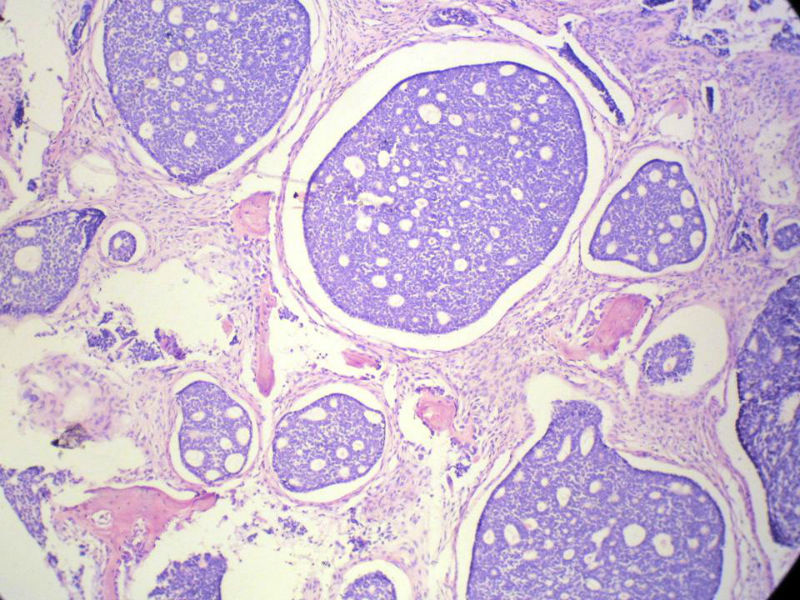

男,76岁,鼻塞两个月,CT提示左上颌窦占位,局部骨质破坏,口腔硬腭下降,局部活检。

左上颌窦占位图2

名称:图2

描述:幻灯片3

腺样囊性癌

腺样囊性癌,图像很典型的